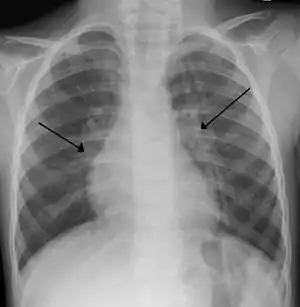

X-ray of a child with RSV bronchiolitis showing the typical bilateral perihilar fullness

Chest x-rays findings in children with RSV bronchiolitis are generally nonspecific and include perihilar markings, patchy hyperinflation, and atelectasis.[8] However, the American Academy of Pediatrics (AAP) does not recommend routine imaging for children with presumed RSV bronchiolitis because it does not change clinical outcomes and is associated with increased antibiotic use.[8][26] Chest x-ray is sometimes considered when the diagnosis of bronchiolitis is unclear or when there is an unexpected worsening.[26] In adults with RSV infection, chest films are often normal or demonstrate nonspecific changes consistent with viral pneumonia, such as patchy bilateral infiltrates.[29]